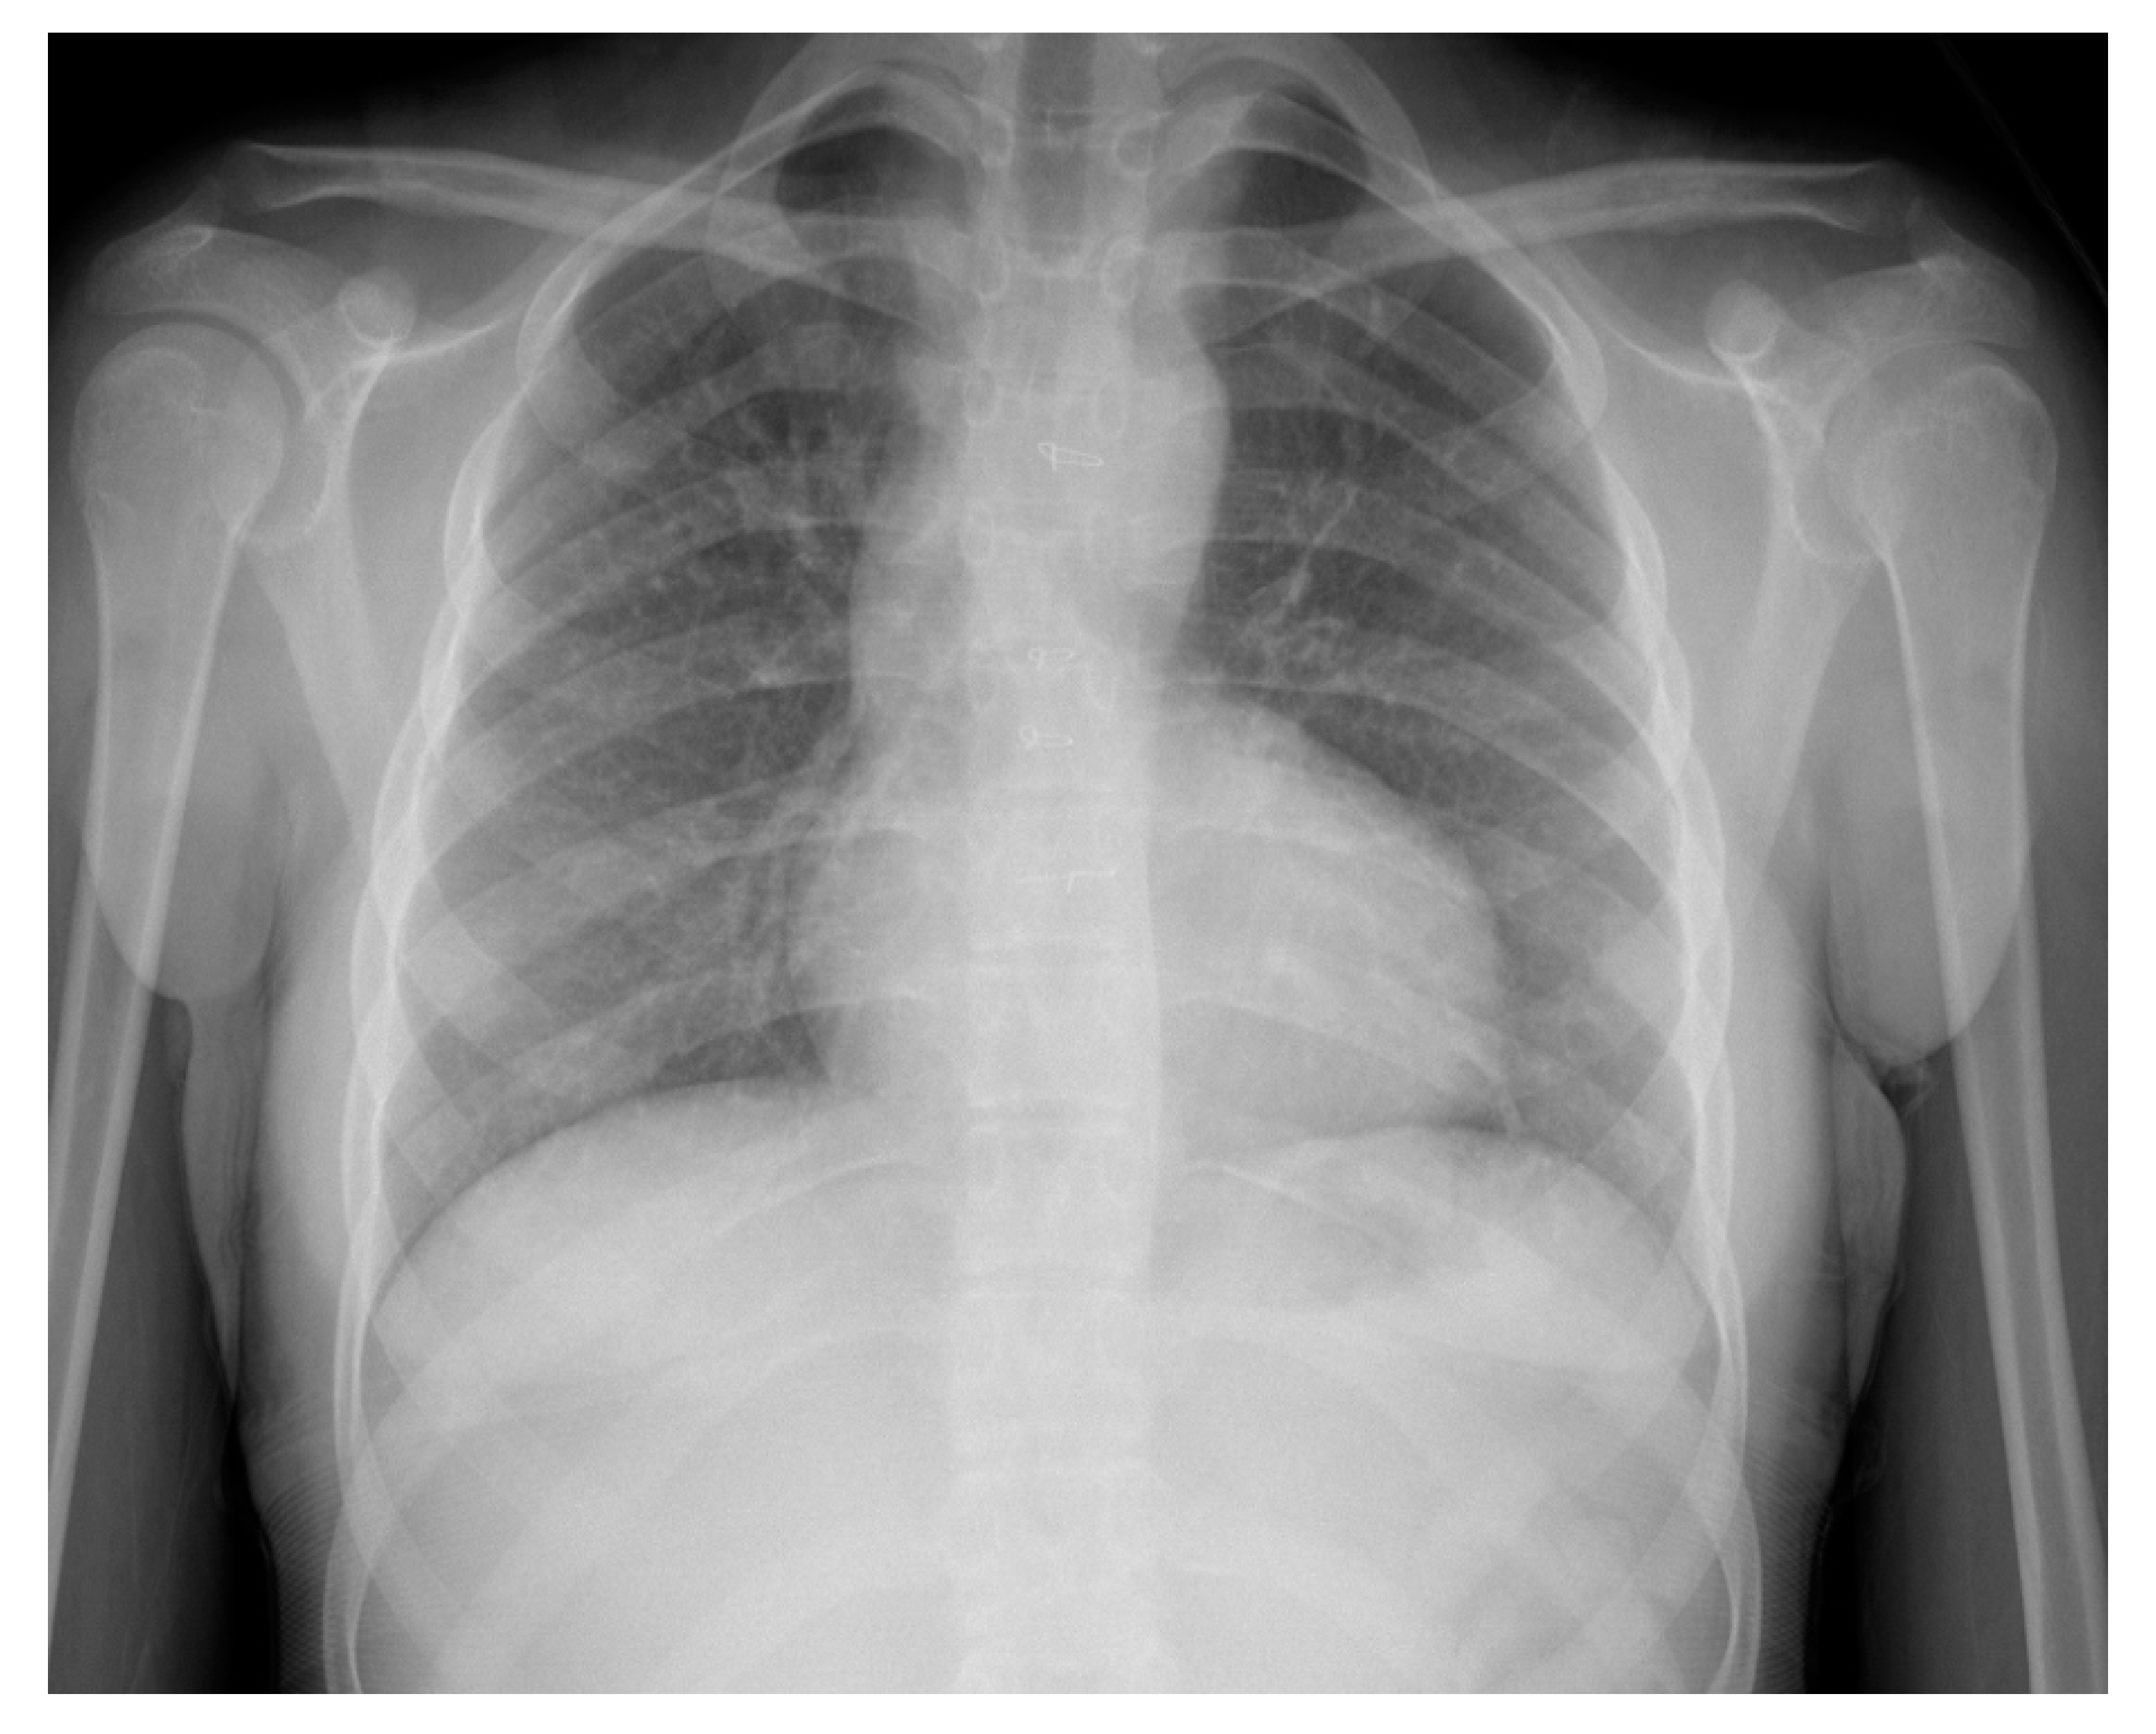

Her ECG showed sinus rhythm and left ventricular hypertrophy (Figure 5). Chest X-Ray showed cardiomegaly with increased bronchovascular markings (Figure 6). Echocardiogram showed mildly dilated and hypertrophied RV with a diastolic septal flattening, normal-sized normal left ventricle, and normal biventricular systolic function. There was severe pulmonary valve regurgitation with mild stenosis of the RV to pulmonary artery conduit with a mean gradient of 40 mmHg. Her CT angiogram (Figure 7) showed no residual ventricular septal defect and mildly dilated aortic root 18 × 17 × 14 mm), moderately to severely dilated ascending aorta (29 × 27 mm) and arch of aorta (27 × 26 mm). Right (11 × 9 mm) and left (15 × 11 mm) pulmonary arteries were mildly dilated. There are stenosis of the right pulmonary artery in distal branches. There were no large MAPCAs. She remained on aspirin only. Cardiac catheterization showed dilated branch pulmonary arteries but stenosis of right branch pulmonary arteries (Figure 8) and hemodynamics revealed normal total PVR. The lung perfusion study showed 65% of flow to left lung compared to 35% to right lung. As there was increased blood flow to the left lung compared to the right lung, changes in the distal pulmonary vasculature were significant in the left lung as shown in Figure 9A compared to right pulmonary vasculature (Figure 9B).

In this case, mild stenosis of distal right pulmonary artery branches lead to relatively less blood supply on the right side compared to increased pulmonary blood flow to the left lung, leading to a flow-related change in pulmonary vasculature (Figure 9B). The perfusion scan confirmed 65% of flow into left and 35% to the right. The patient is scheduled for genetic evaluation of aortopathy as the cause of aortic root and arch is unknown. No targeted PH therapy is started as this could cause increased flow to the unobstructed pulmonary segments and further increase flow-related PVD. She is scheduled for a repeat CT angiogram in near future for possible intervention of left branch pulmonary artery stenosis.

Figure 9. Digital subtraction angiography of left pulmonary artery (LPA) (A) compared right pulmonary artery (RPA) (B); (A) Arrow pointing to pruning of distal pulmonary vasculature on left; (B) Arrow pointing to normal distal pulmonary vascular arborization pattern on right.